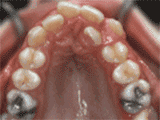

1、牙列擁擠

這類人,由于牙量與骨量不匹配,造成牙齒畸形,因此,在矯牙時,必須拔掉一定數(shù)量的牙,以協(xié)調(diào)牙量與骨量的關系,解除牙列擁擠的狀況,減少畸形復發(fā)。